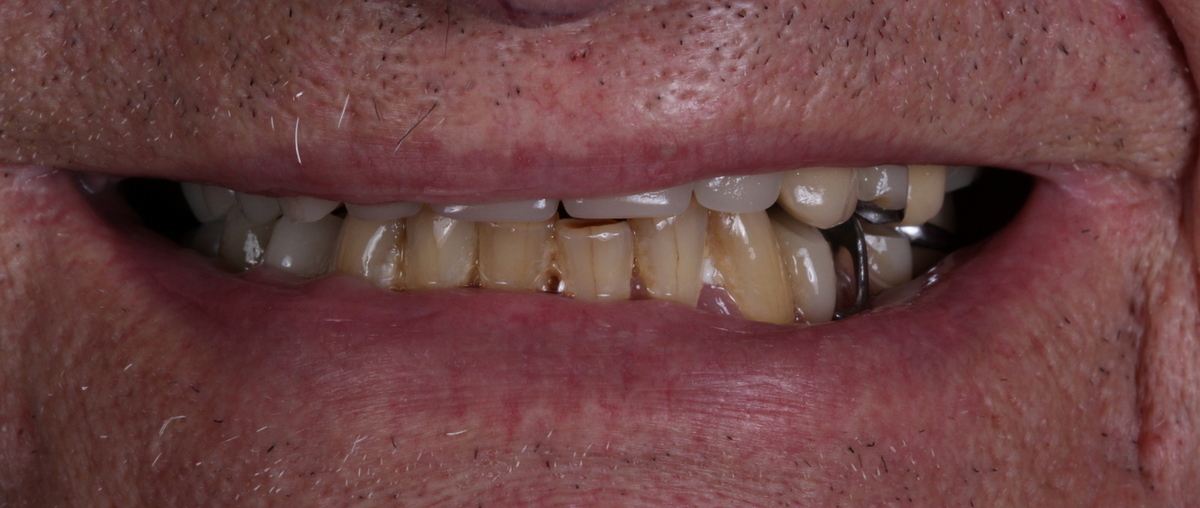

PRÓTESE TOTAL FIXA EM IMPLANTES

R.A.A.